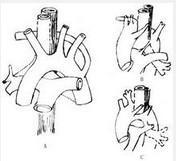

腹部大血管损伤

628健康网为您分享有关腹部大血管损伤的症状,腹部大血管损伤的治疗方法,腹部大血管损伤的预防知识,腹部大血管损伤的症状...

腹主动脉瘤

628健康网为您分享有关腹主动脉瘤的症状,腹主动脉瘤的治疗方法,腹主动脉瘤的预防知识,腹主动脉瘤的症状图片,腹主动脉瘤...

感染性腹主动脉瘤

628健康网为您分享有关感染性腹主动脉瘤的症状,感染性腹主动脉瘤的治疗方法,感染性腹主动脉瘤的预防知识,感染性腹主动脉...